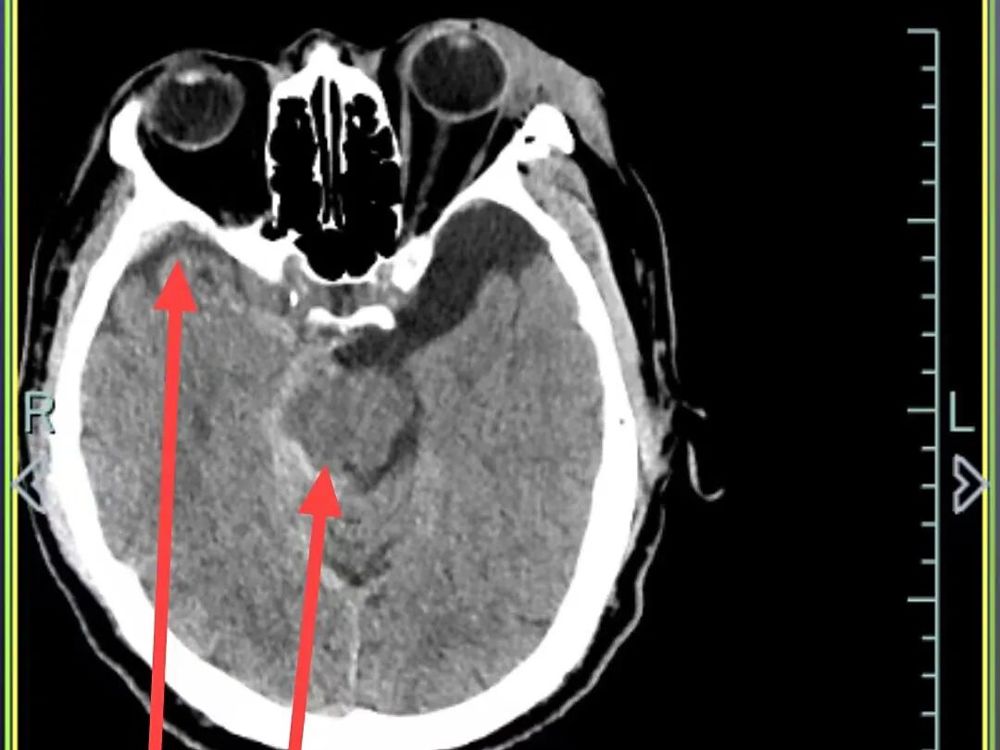

△10月4日CT复查显示,孙先生颅内出血全部吸收,骨折位置没有移位

医院快速开通绿色通道并完善一系列检查后,诊断结果令人揪心:孙先生患有重型闭合性颅脑损伤,包括多发性创伤性脑出血、右侧颞部创伤性硬膜下出血、创伤性蛛网膜下腔出血以及脑震荡,同时合并多处骨折及软组织挫裂伤。

硬膜下出血、蛛网膜下腔出血和多发性创伤性脑出血